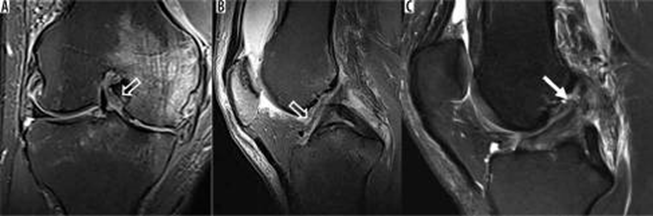

Trước đây được chẩn đoán là hoại tử xương tự phát của đầu gối, hiện nay thực thể này được công nhận là gãy xương do suy xương dưới sụn, có thể xảy ra kèm theo hoặc không kèm theo hoại tử thứ phát. Gãy xương do suy xương dưới sụn thường xảy ra ở những bệnh nhân cao tuổi hoặc loãng xương (tuổi trung bình là 70), những người có xương bị yếu cơ học [18]. Trên cộng hưởng từ, có một đường đứt gãy tuyến tính có cường độ tín hiệu thấp bên dưới bề mặt khớp xương đùi xa hoặc gần xương chày trên hình ảnh T1W (cổ điển là đường viền xương đùi giữa) với cường độ tín hiệu giống như phù tủy xương lân cận, rõ rệt trên hình ảnh T2W xóa mỡ [18]. Đôi khi, đường gãy có thể rất nhỏ và gần với mảng xương dưới sụn đến mức có thể không nhìn thấy được, và gãy xương do suy dưới sụn nhỏ có thể chỉ xuất hiện dưới dạng những vùng xơ cứng nhỏ. Sụn bên dưới thường nguyên vẹn, trừ khi có thoái hóa màng đệm từ trước. Chẩn đoán MRI đối với những tổn thương này là quan trọng vì điều trị mang tính bảo tồn với những hạn chế về trọng lượng.

Hình 16. Phù tủy xương và Gãy xương dưới sụn. Hình ảnh pd xóa mỡ coronal với cường độ tín hiệu thấp tuyến tính (mũi tên) bên dưới bề mặt khớp chịu trọng lượng của ống sống giữa xương đùi, phù hợp với gãy xương kèm theo phù tủy xương dưới sụn. -như tín hiệu. Sụn bên dưới còn nguyên vẹn, ngoại trừ thoái hóa sụn chêm ở mức độ trung bình từ trước.